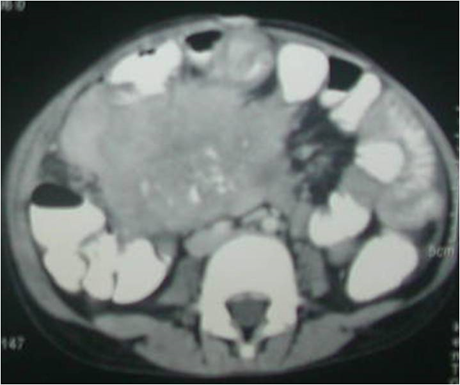

A 7 year-old girl was admitted with lower abdominal lump of six months duration. There was an 8x6cm well-defined firm, smooth, mobile and ovoid lump on the right side of the umbilicus. Chest and abdominal X-rays were normal. Abdominal ultrasound (USG) showed a 10x8x6cm mass in the right side of abdomen, with calcifications and vascularity. Computed Tomography (CT) abdomen revealed an 8.8x7.2x5.4cm ill-defined heterogeneous, enhancing lesion, mostly neoplastic, arising from the mesentery and encasing the small bowel with areas of soft tissue, fat attenuations and calcifications (Figure 1). USG-guided biopsy showed spindle shaped cells on a background of inflammatory infiltrate suggestive of IMT. At laparotomy, a 12x10x8cm firm to hard mesenteric mass, densely adherent to and encasing the ileal loops was found. Complete excision of mass with resection of the adherent bowel and ileo-transverse anastomosis was done. Histopathology revealed that the tumor was composed of interlacing fascicles of elongated spindle cells mixed with plasma cells, histiocytes, lymphocytes and eosinophils, suggestive of IMT. The patient is asymptomatic on follow-up.

Figure 1: Computed Tomography (CT) Scan of the patient showing an 8.8x7.2x5.4cm ill-defined heterogeneous, enhancing lesion, mostly neoplastic, arising from the mesentery and encasing the small bowel; Areas of soft tissue, fat attenuations and calcifications can be seen.